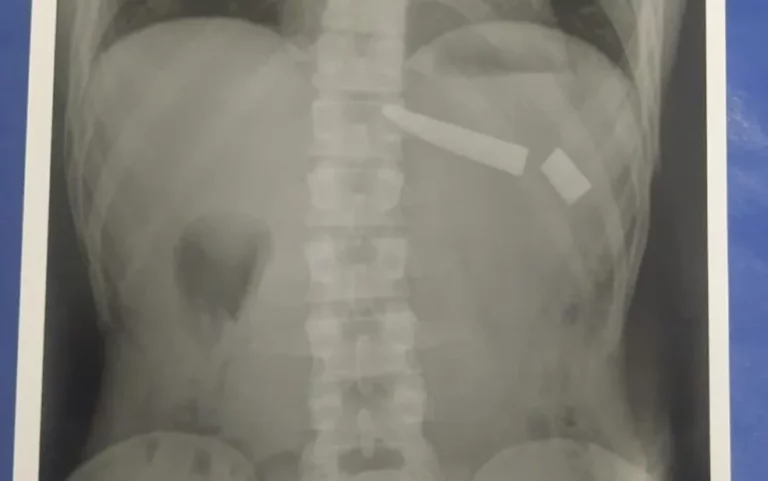

Um jovem de 25 anos precisou passar por cirurgia nesta quarta-feira (4) após uma faca quebrar dentro dele, em Goiânia. Segundo a Polícia Militar, ele estava brigando com a esposa quando um homem interveio e eles começaram a brigar. Durante a discussão, o suspeito o esfaqueou nas costas e na região dos rins. Segundo a polícia, a faca quebrou em dois lugares do tórax.

À polícia, o suspeito contou que os dois chegaram a “rolar o chão” durante a briga e que ele tomou a faca da mão do jovem e deu duas facadas superficiais nele. Após ser atingido, o jovem saiu correndo e pediu socorro para um vizinho. Os policiais informaram que quando chegaram no local, no Jardim Abaporu, o jovem estava caído no chão.

Ele foi socorrido pelo Serviço de Atendimento Móvel de Urgência (Samu) e encaminhado para o Hospital de Urgências de Goiás (Hugo). Segundo o hospital, o paciente já passou por cirurgia e está se recuperando.